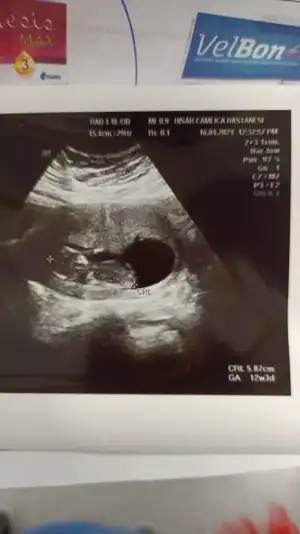

Kız görünüyorBizede bakabilir misin rica etsem ilk bebeğimizEki Görüntüle 2825129

Bizede bakarmısın 12 haftalık bebeğimKız görünüyor